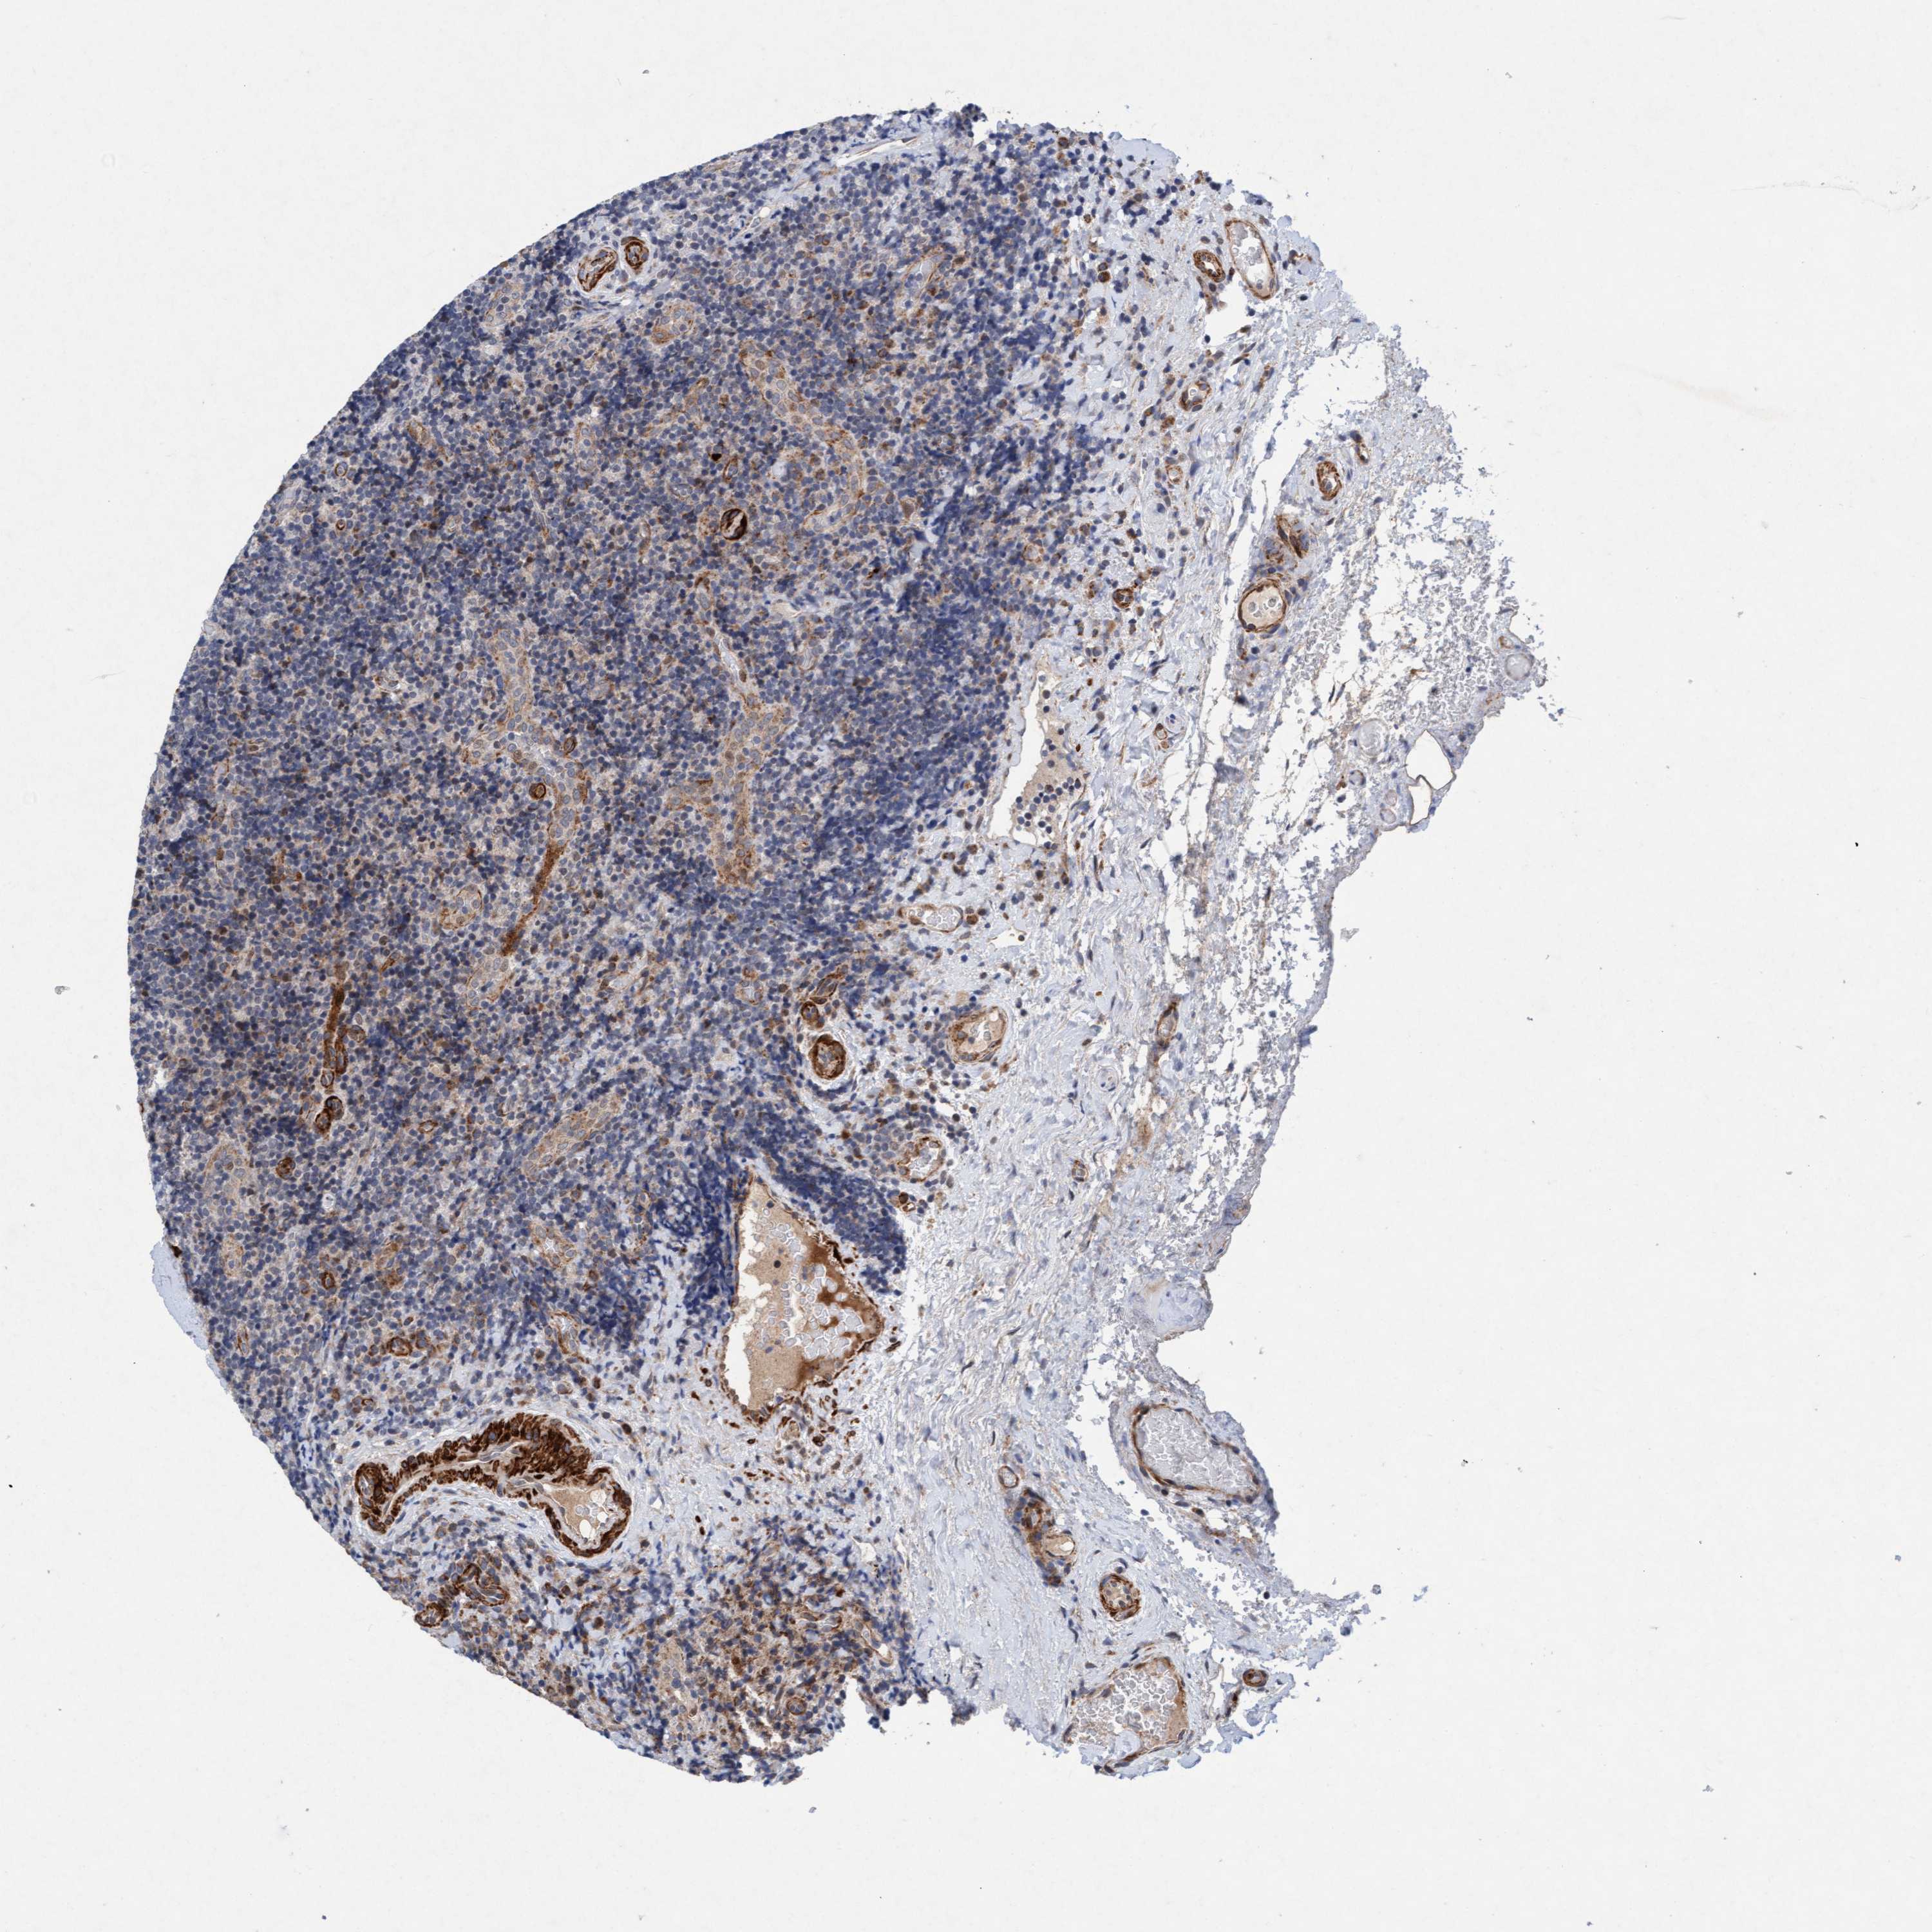

LYMPHOMA - Protein expressioni

A mouse-over function shows sample information and annotation data. Click on an image to view it in a full screen mode. Samples can be filtered based on level of antibody staining by selecting one or several of the following categories: high, medium, low and not detected. The assay and annotation is described here.

Each image is clickable and will lead to virtual microscopy that enables deeper exploration of all samples and also displays staining intensity scores, fraction scores and subcellular localization as well as patient and tissue information for each sample.

Antibody HPA023187

Antibody CAB034226

Staining

High

Medium

Low

Not detected

Intensity

Strong

Moderate

Weak

Negative

Quantity

>75%

75%-25%

<25%

None

Location

Nuclear

Cytoplasmic/membranous

Cytoplasmic/membranous,nuclear

Hodgkin's disease, NOS

Malignant lymphoma, non-Hodgkin's type, High grade

Malignant lymphoma, non-Hodgkin's type, Low grade